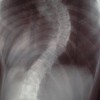

メンバー 161ノート 138

手術をしたくない方必見。ヘルニア、脊柱管狭窄症、脊椎すべり症はすべて、腰のS字カーブ(生理的弯曲わんきょく)が崩れて腰の骨格の角度がおかしいために、圧力が高まって起きます。名前は違えど原因は同じです。その原因をそのままにして、根本的解決は目指せません。このオープンチャットでは、施術師のリザが上記症状を解消する考え方と何をすべきかをお伝えしています。根本的な治療をお探しの方はご参加ください。 ※あくまでも臨床の現場で得た知見をお伝えする場です。すべての医療関係者やカイロプラクターの共通見解というわけではありません。 #腰椎 #腰椎ヘルニア #ヘルニア #脊柱管狭窄症 #骨 #椎間板ヘルニア #脊椎 #圧迫 #麻痺 #痺れ #痛み #整形外科 #整形 #手術 #神経圧迫 #神経 #カイロ #整体 #ぎっくり腰 #ギックリ腰 #鍼  #灸